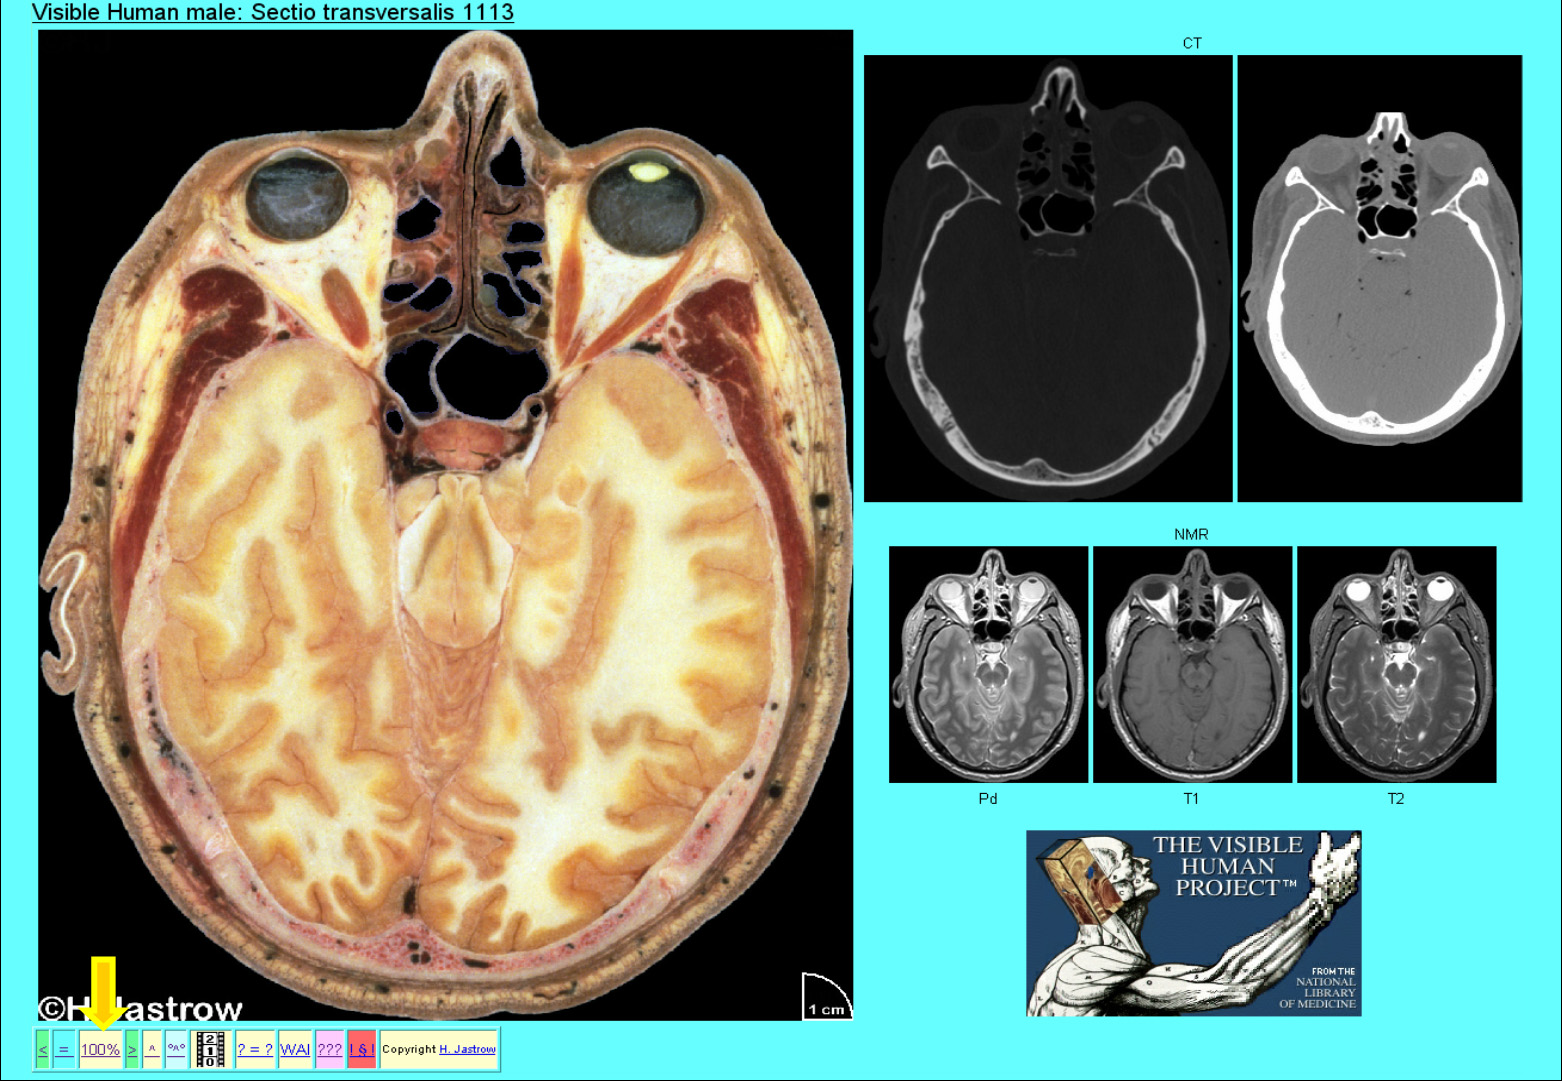

1991 erhielt die Universität des US Bundesstaates Colorado 1,4 Mio. US Dollar zur Verwirklichung des Projektes „sichtbarer Mensch“ (Abb.3). Das Ziel dabei war die Schaffung hochwertiger digitaler menschlicher Schnitte, die eine 3-dimensionale Veranschaulichung des normalen Aufbaus des menschlichen Körpers ermöglichen. Zugehörige radiologische Aufnahmen zeigen wie Strukturen von Röntgenbildern, Computertomographien und Kernspinresonanztomographien in Wirklichkeit aussehen. Die Originaldaten stehen der Öffentlichkeit zur Verfügung und umfassen für jedes Geschlecht je einen Datensatz. Von der Homepage des Projekts aus kann man informieren über einen Großteil dessen was für die medizinische Ausbildung aber auch für interessierte Laien geschaffen wurde.

Eines dieser Produkte ist der Homo sapiens dissecatus. Dieser Atlas beinhaltet das gesamte Bildmaterial des Mannes (Abb.4). Der zugehörige Originaldatensatz umfasst in komprimierter Form ca. 39 GB. Das sind 55 randvolle CDs. Hier sehen Sie technische Details dazu. Weitere finden Sie auf Ihrem Informationsblatt. Das faszinierende ist, dass alle Daten vom selben Individuum stammen, daher entsprechen z.B. die unten gezeigten radiologischen Bilder dem oben demonstrierten Schnitt durch das Gehirn.

Es wird die in Abb.21 gezeigte Übersichtsseite geladen. Die Drüse ist auf den hervorgehobenen Schnitten zu erkennen. Wenn wir auf das markierte Miniaturbild klicken, erscheint die Seite mit dem digitalisierten Schnitt und den zugehörigen CT und NMR Aufnahmen (Abb.22). Um mehr erkennen zu können, klicken wir den 100% Knopf an. Abb.22

In Abb.27 sehen Sie eine Seite des Brustraums mit den zugehörigen CT und NMR Abbildungen. Man erkennt die beiden Herzkammern, den rechten Vorhof und die Lungen, die Wirbelsäule, Rippen und Muskeln der Oberarme.